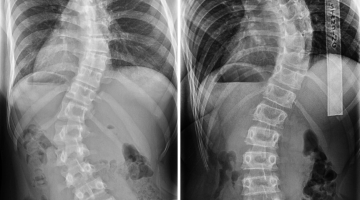

Σε ένα άνετο και εύκολα προσβάσιμο χώρο φτιαγμένο με απόλυτο γνώμονα τον άνθρωπο ο Αδνάν Ναλμπάντ, απόφοιτος του Τμήματος Φυσικοθεραπείας του ΤΕΙ Αθήνας, μεταπτυχιακό Ιατρικής σχολής ΔΠΘ, με εξειδίκευση στην Μηχανική Διάγνωση και Θεραπεία (McKenzie), στην μέθοδο Schroth για την σκολίωση και κύφωση αλλά και στην Φυσικοθεραπεία Πυελικού Εδάφους (Men's Health Physiotherapy). Mε πολυετή εμπειρία στο δημόσιο και ιδιωτικό τομέα, αλλά και στο εξωτερικό, με διδακτική εμπειρία σε ΙΕΚ , άνοιξε το νέο του Φυσικοθεραπευτήριο στην Κομοτηνή επί της οδού Όθωνος 2 έναντι Arena Parking

φυσικοθεραπεία, φυσικοθεραπευτής, φυσικοθεραπευτές, εοπυυ, φυσικοθεραπευτής εοπυυ, ισχιαλγία, οσφιαλγία, αυχενικό, φυσικοθεραπεία πυελικού εδάφους, ακράτεια, φυσικοθεραπευτες κομοτηνη, φυσικοθεραπεια κομοτηνη, φυσικοθεραπεια, φυσικοθεραπευτης, schroth, σκολίωση, κύφωση, McKenzie